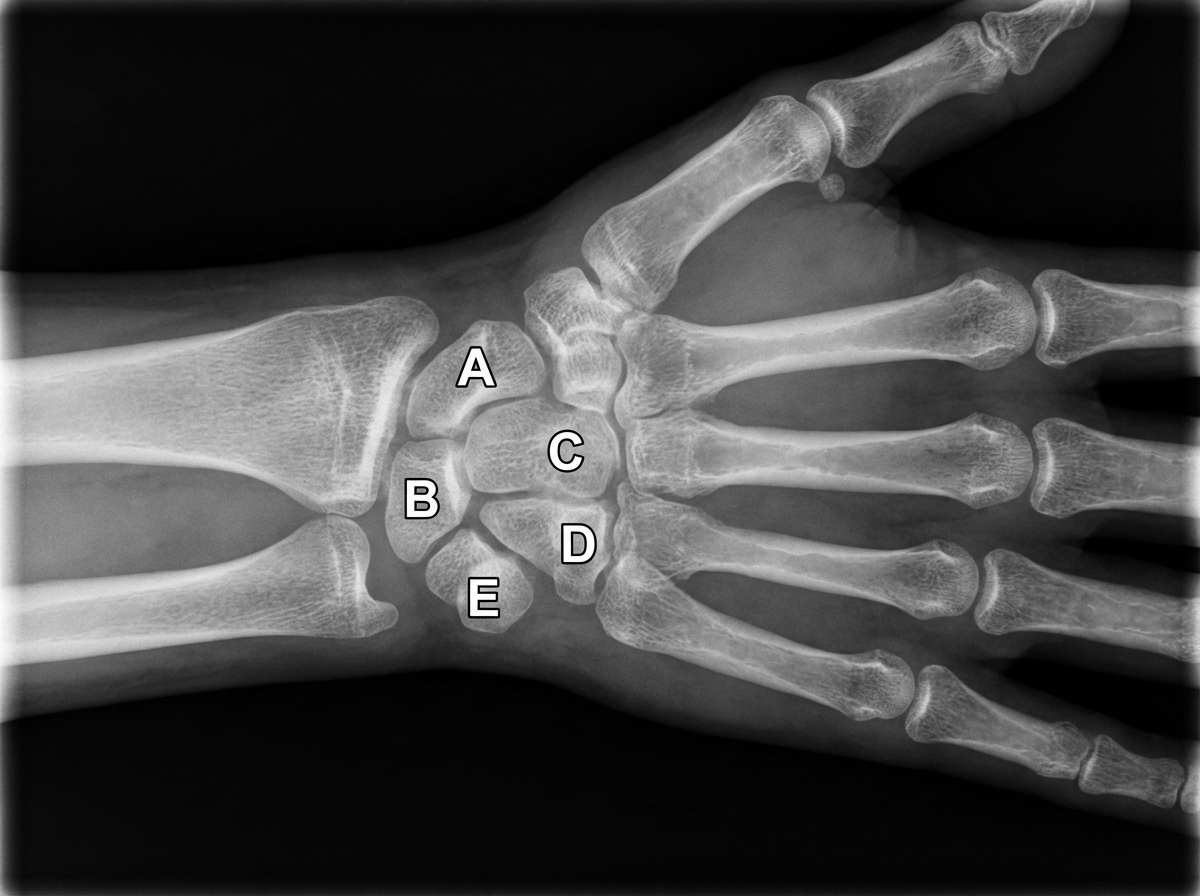

Destruction of the structure indicated by the letter E in the radiograph of the wrist and hand most likely causes weakness of which of the following muscles?

Explanation: ***Flexor carpi ulnaris*** - Structure E in the wrist radiograph is the **pisiform bone**, which serves as the primary insertion site for the **flexor carpi ulnaris (FCU)** muscle. - Destruction of the pisiform bone would directly compromise the **mechanical advantage** and strength of the FCU, leading to weakness in wrist flexion and ulnar deviation. *Flexor carpi radialis* - This muscle inserts at the **base of the second and third metacarpals**, not at the pisiform bone (structure E). - Destruction of the pisiform would not directly affect the **flexor carpi radialis** as it has a separate insertion site on the radial side of the wrist. *Palmaris longus* - The palmaris longus inserts into the **palmar aponeurosis** and **flexor retinaculum**, not the pisiform bone. - This muscle would remain functionally intact even with pisiform destruction, as its insertion is in the **central palm** rather than at bony landmarks. *Brachioradialis* - This muscle inserts at the **styloid process of the radius**, which is located on the lateral (radial) aspect of the forearm. - The **brachioradialis** is primarily a **forearm flexor** and would be unaffected by pisiform bone destruction on the ulnar side of the wrist.